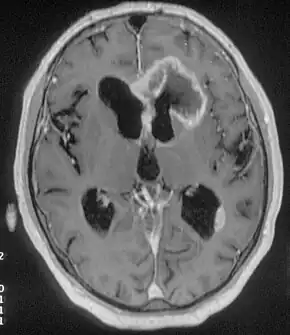

Causes may include genetics, malformed areas of brain, brain tumors, and injury.[2] They often only occur while the person is sleeping.[5][6] They arise from the frontal lobe of the brain.[2] Diagnosis may be based on symptoms.[2] In around 66% of cases MRI finds abnormalities, while an EEG often adds little.[2] Positron emission tomography (PET) or single photon emission CT (SPECT) may also help localize the area affected.[3] Other conditions that may appear similar include psychogenic non-epileptic seizures (PNES), and sleep disorders.[1][3]

Neuroimaging

Advancements in technology, has given rise to newer, more efficient methods of diagnosis, most prominent being in the domain of neuroimaging.[18] The high spatial resolution from fMRI has implications on certain brain regions contributing to memory.[18] The usage of task fMRI for examination of memory or other higher cognitive networks may also be used to predict ictal onset zone(s) in patients with FLE, giving the advantage of refinement of patient-specific analyses.[18] The use of multi-modal approaches in association with neuroimaging techniques like fMRI and MEG or EEG will be informative in characterizing atypical functional brain networks in FLE.[18] But, difficulty remains in the evaluation of potential compensatory mechanisms between patients with FLE with normal and impaired memory, without properly characterizing transfer of information during memory tasks.[18]

Positron emission tomography (PET) helps to locate epileptogenic loci.[9] If the MRI were normal the PET scan could locate some abnormalities.[9]